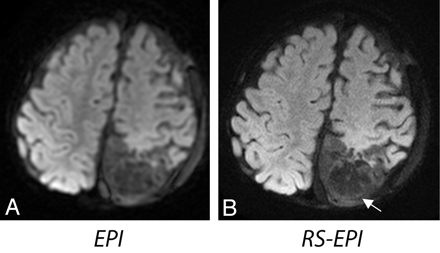

RS-EPI also reduced distortion in areas adjacent to tissue-air or bone interfaces from signal-intensity pile-up effects (Fig 6A, -B) and gave increased diagnostic confidence in areas adjacent to the auditory canal in a patient with tumor (Fig 7). In several patients, EPI had elevated gray/white matter contrast on iso-DWI due to a more pronounced T2 shinethrough effect from the longer TE of EPI as shown in Fig 8 (note that this did not occur for RS-EPI even though RS-EPI used twice-refocused diffusion preparation which prolongs TE). These equivocal signal-intensity high intensities occasionally led to a decreased diagnostic confidence level.

Two sections from a patient with diffuse infiltrating anaplastic astrocytoma (a 14-year-old girl). A and B, DWI shows areas of increased cellularity (open white arrow). C and D, Areas of increased signal intensity on EPI (white arrow) suggest the possibility of cortical and subcortical tumor involvement, which may be seen with gliomatosis or diffuse infiltrating glioma. Reduction of distortion in RS-EPI shows a normal cortical ribbon. Also, the open arrows show areas of increased distortion on EPI compared with RS-EPI.

Two sections from an 8-year-old female patient. A, Distortion artifacts on EPI could be confused with subdural hemorrhage or empyema. This artifact disappears on RS-EPI (B). A,C, Elevated contrast on EPI, not appearent on RS-EPI (B,D), could be confused with diffuse cortical ischemic injury, encephalitis, or even seizure-related changes.